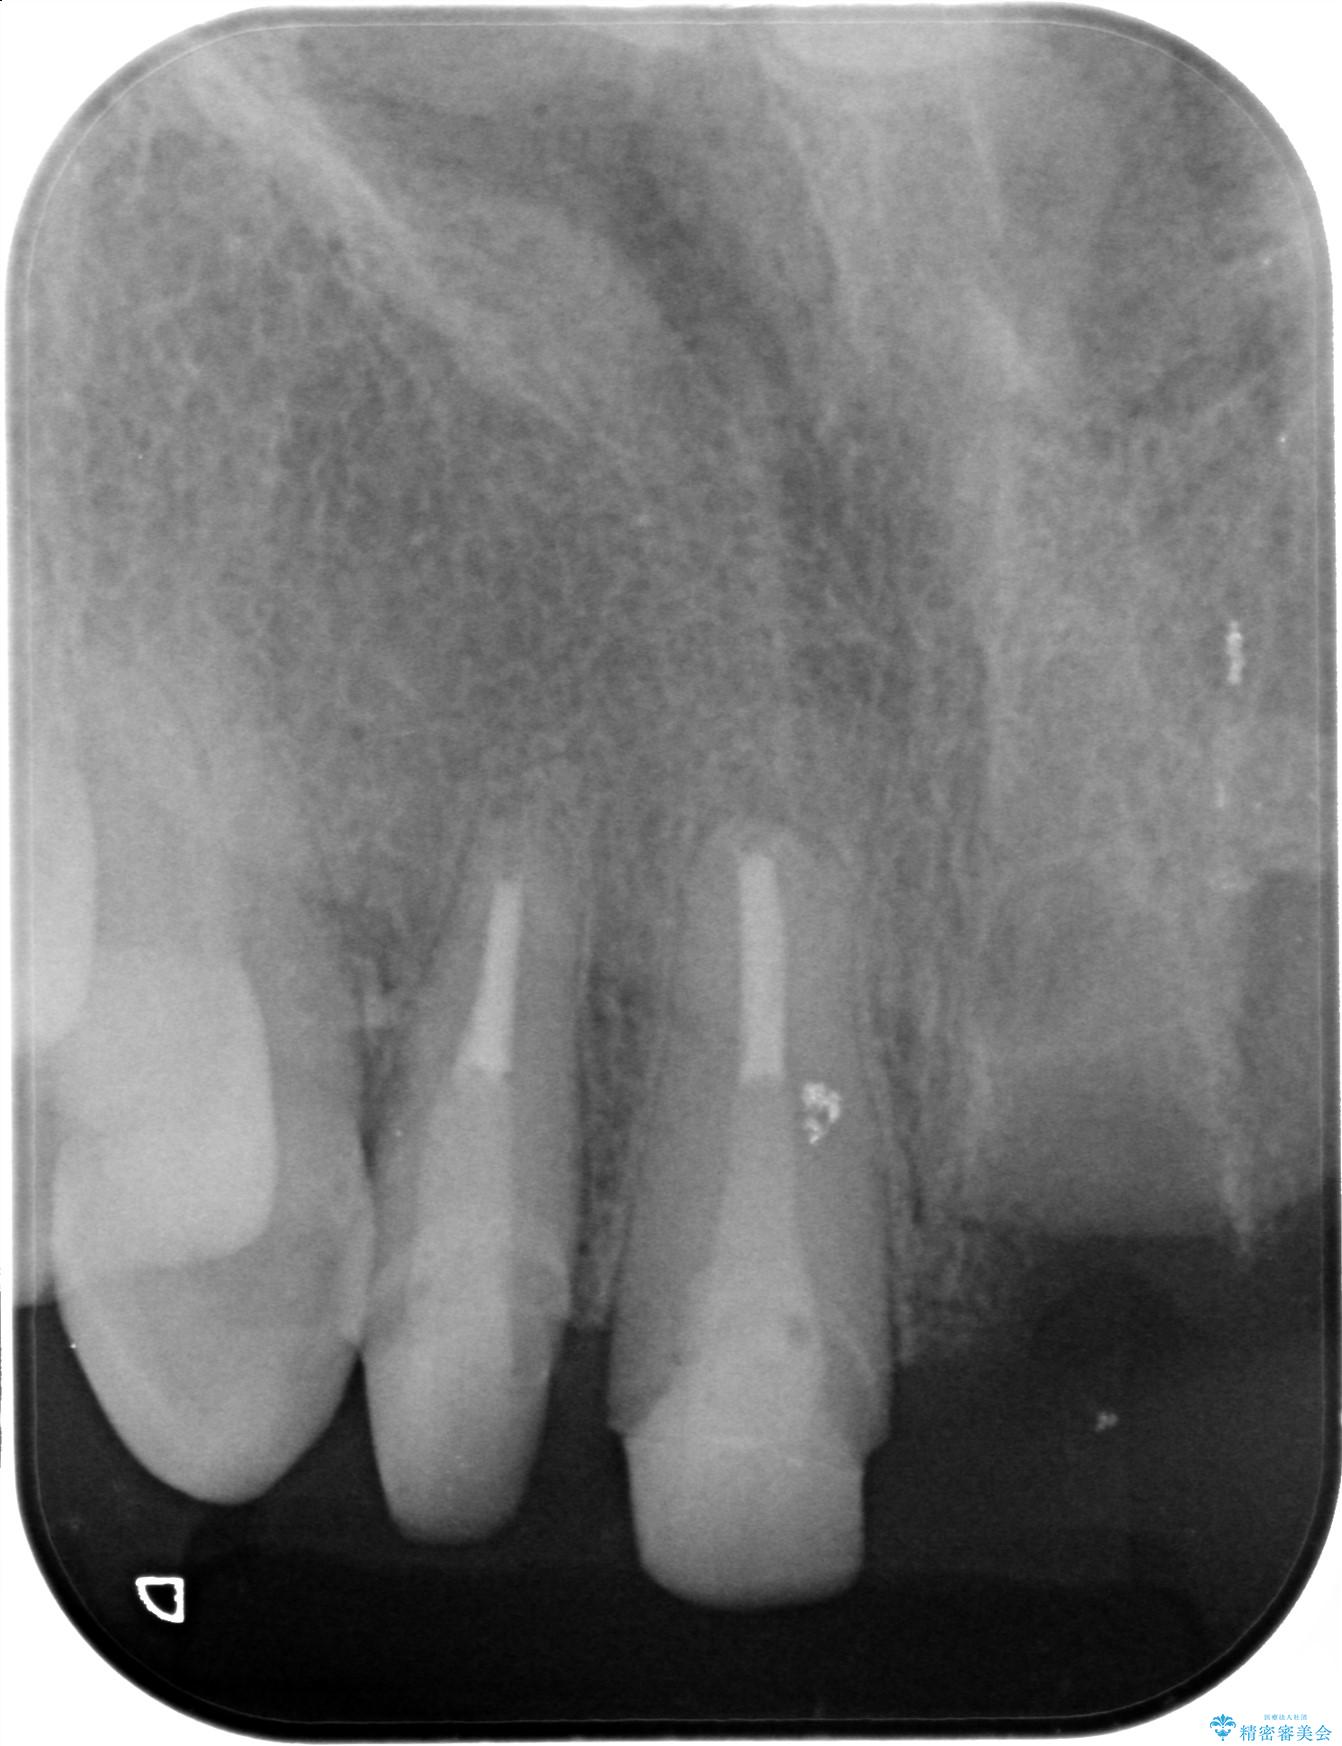

治療前

歯槽堤保存術を併用したブリッジ治療 治療前画像 歯槽堤保存術を併用したブリッジ治療 治療前画像 歯槽堤保存術を併用したブリッジ治療 治療前画像 歯槽堤保存術を併用したブリッジ治療 治療前画像 歯槽堤保存術を併用したブリッジ治療 治療前画像 歯槽堤保存術を併用したブリッジ治療 治療前画像 歯槽堤保存術を併用したブリッジ治療 治療前画像 歯槽堤保存術を併用したブリッジ治療 治療前画像 歯槽堤保存術を併用したブリッジ治療 治療前画像 歯槽堤保存術を併用したブリッジ治療 治療前画像